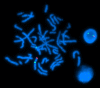

A 46,XX male represents a variant of Klinefelter syndrome (47,XXY), under the category of a disorder of sex development (DSD). Despite possessing an XX karyotype, these individuals exhibit a male phenotype, which, in this case, results from a translocation of the SRY gene from the Y chromosome onto the X chromosome. This genetic alteration results in the development of male gonadal characteristics. This case report outlines a prenatal diagnosis of a 46,XX female in conflict with a level 2 ultrasound. It details the patient's presentation, diagnosis of an SRY-positive 46,XX male, and medical history. The discussion focuses on the advantages of early identification and intervention in managing symptom progression and addressing fertility challenges through hormone replacement therapy. Further exploration of 46,XX DSD early detection and the underlying mechanisms is essential for refining diagnostic and therapeutic approaches that result in a greater quality of life for these patients.